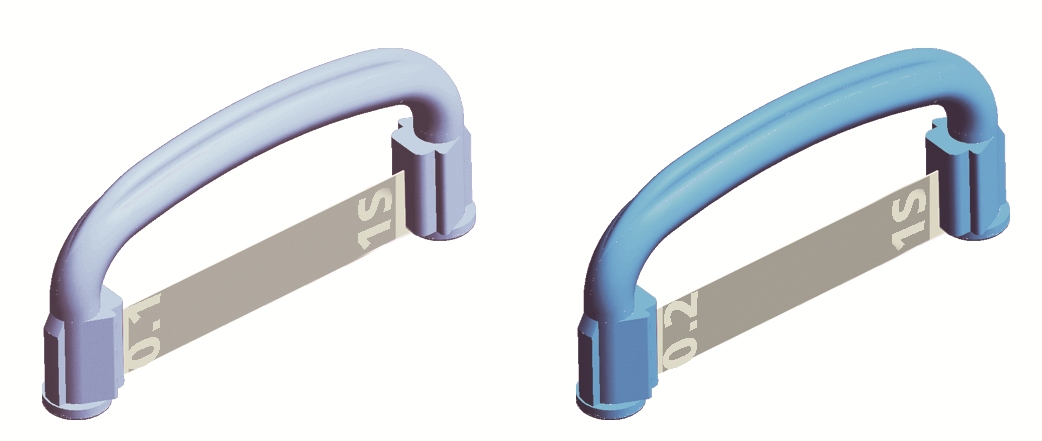

Limes de stripping G5-PROLIGN

Description

- Morbi in sem quis dui placerat ornare. Pellentesque odio nisi, euismod in, pharetra a, ultricies in, diam. Sed arcu. Cras consequat.

- Praesent dapibus, neque id cursus faucibus, tortor neque egestas augue, eu vulputate magna eros eu erat. Aliquam erat volutpat. Nam dui mi, tincidunt quis, accumsan porttitor, facilisis luctus, metus.